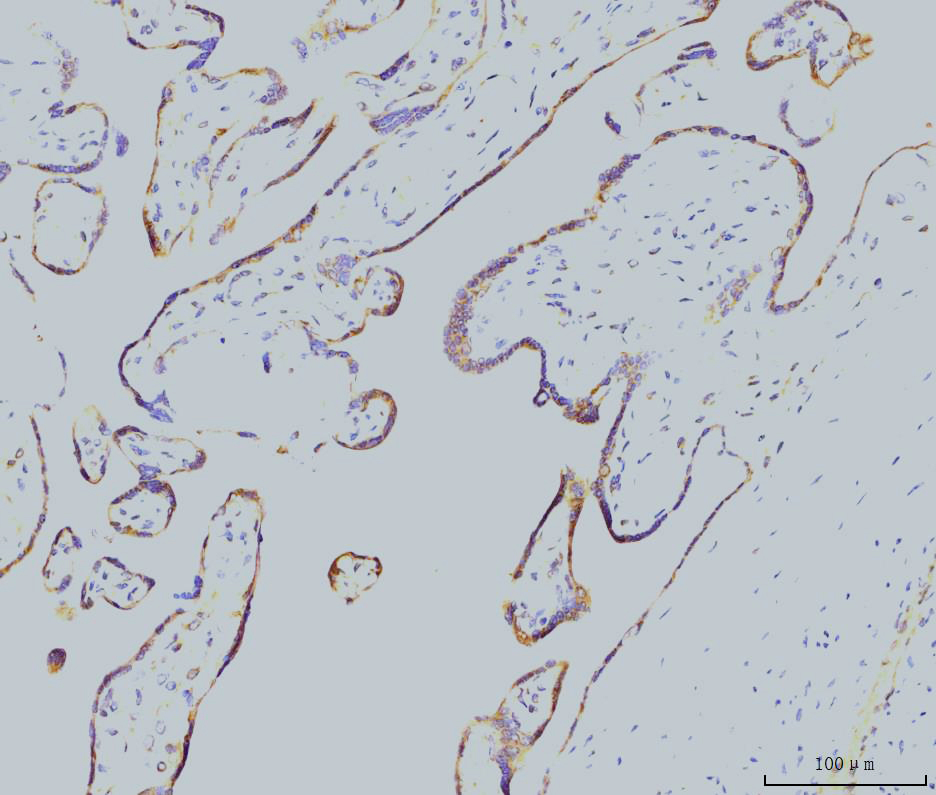

IHC analysis of RAB11A using anti-RAB11A antibody (M01436-2).

RAB11A was detected in a paraffin-embedded section of human placenta tissue. Biotinylated goat anti-mouse IgG was used as secondary antibody. The tissue section was incubated with mouse anti-RAB11A Antibody (M01436-2) at a dilution of 1:200 and developed using Strepavidin-Biotin-Complex (SABC) (Catalog # SA1021) with DAB (Catalog # AR1027) as the chromogen.